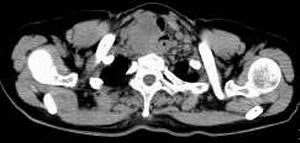

女,61岁,吞咽困难(包括开水)已久。

食道中上段癌并锁骨上窝淋巴结转移.

3、右侧甲状腺是否有问题?是否甲状腺ca转移食道上段。因为肿块顶部图像没有,请楼主展示,谢谢!

食道中上段中分化鳞癌伴锁骨上淋巴结转移